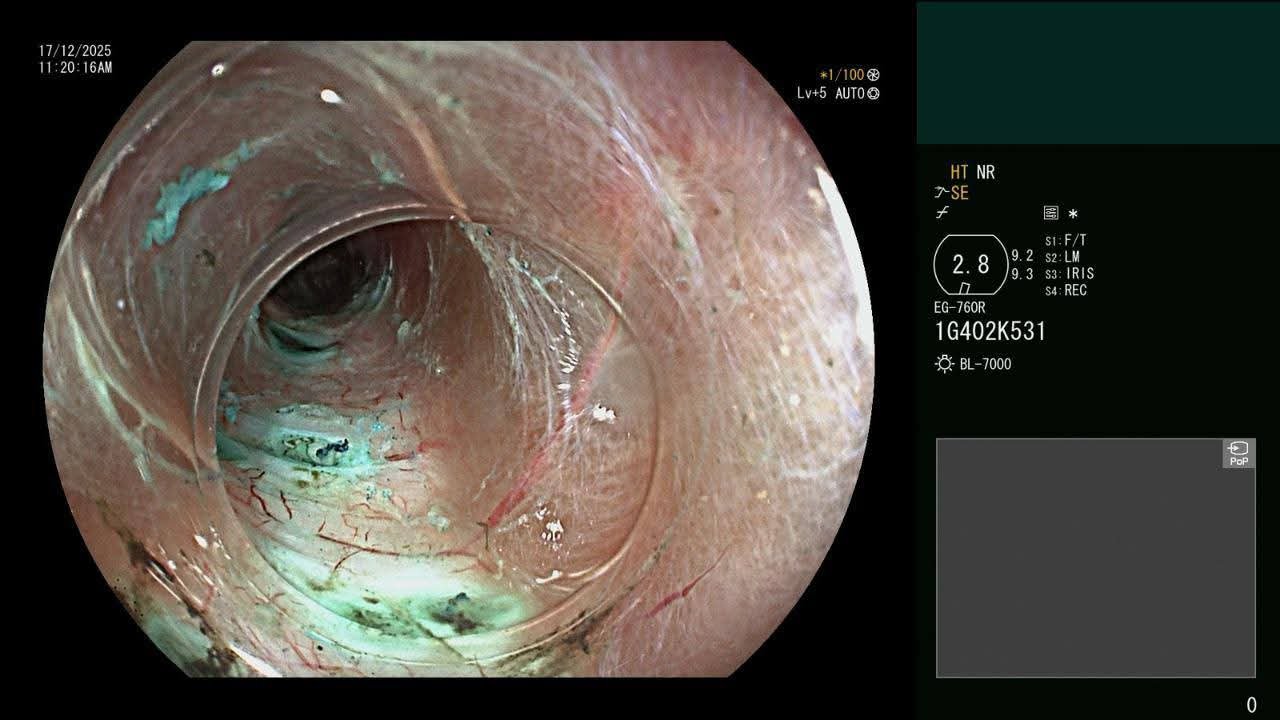

أجرى قسم جراحة الأطفال بالتعاون مع قسم الجهاز الهضمي والكبد بمستشفى سيد جلال الجامعي بطب الأزهر عملية تدخل علاجي دقيق بتقنية شق عضلة المريء بالمنظار (Per Oral Endoscopic Myotomy – POEM) لطفلة تبلغ من العمر عامين فقط وبوزن ٩ كجم.

ثم تم إجراء العملية بوحدة مناظير الجهاز الهضمي بقسم الكبد والجهاز الهضمي، بالتعاون مع فريق قسم جراحة الأطفال، والتي استغرقت نحو ٣٠ دقيقة فقط، بنجاح تام دون حدوث أي مضاعفات أثناء أو بعد إجراء العملية، مع تحسن ملحوظ وسريع في البلع، وخروج الحالة بسلام من قسم جراحة الأطفال بعد التأكد من نجاح التدخل واستقرار الحالة العامة.

وتُعد هذه الحالة Case Report علميًّا؛ حيث تُصنف باعتبارها من الحالات النادرة التي يتم فيها تطبيق تقنية POEM لطفل يقل عمره عن ٣ سنوات ووزنه أقل من ١٠ كجم، وهو ما يمثل إضافة علمية وطبية متميزة باسم مستشفيات جامعة الأزهر بما يعزز من مكانة الجامعة إقليميًّا ودوليًّا في مجال مناظير الجهاز الهضمي العلاجية المتقدمة والتدخلات فائقة الدقة بالمنظار.